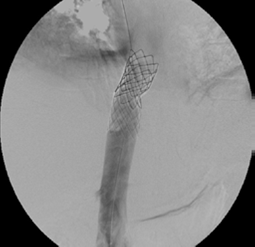

Se procedió a realizar angioplastias secuenciales con balones de 10, 12 y 14 mm de diámetro (Boston Sci. Corp.), logrando repermeabilizar la vena cava, pero con una estenosis residual del 60 % (figura 5). Se continuó colocando dos endoprótesis (stents) de Palmaz con balón montado de 24 mm de diámetro (Cordis™ - Johnson & Johnson). La vena cava se recanalizó de manera completa y las venas suprahepáticas eran permeables (figura 6).